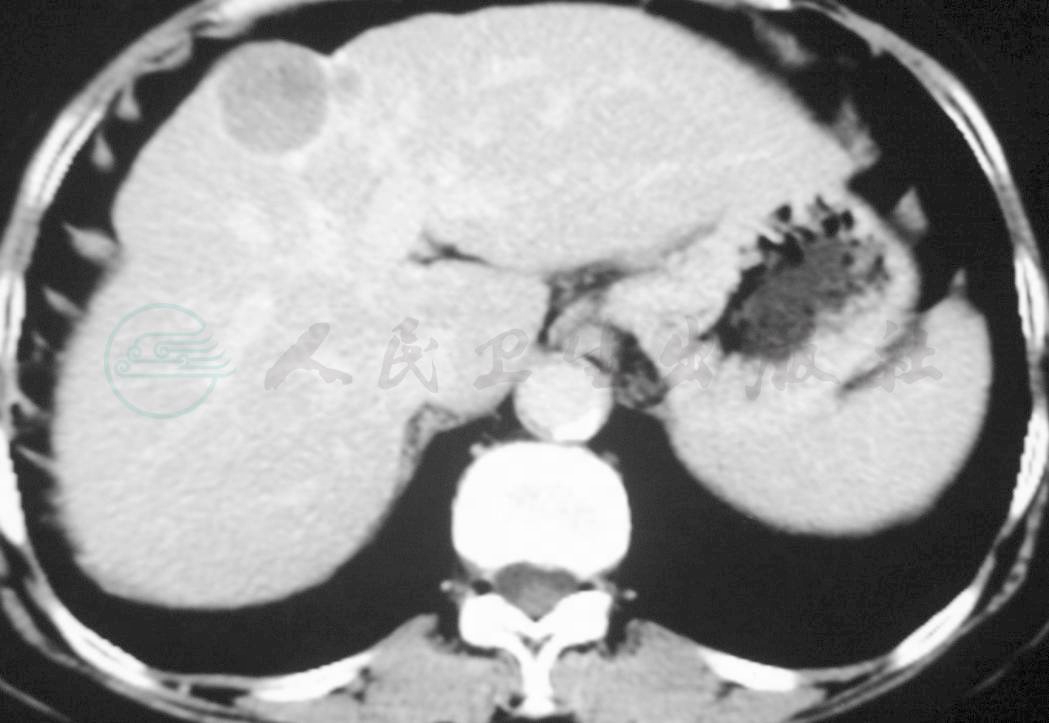

2.术前肝脏CT

提示肝脏膈顶部肿物,影像学表现符合原发性肝癌,周围伴子灶(图1)。

图1 Ⅳ、Ⅷ段交界肝脏肿瘤,大小4.5cm×4.0cm,另距肿瘤左侧1cm处可见一子灶,大小1.0cm×0.8cm